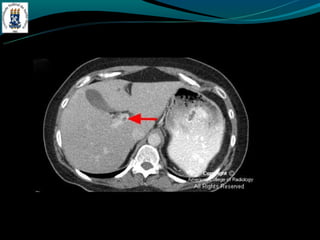

TROMBOSE DA VEIA PORTA

-Complicação de cirrose

-Invasão ou compressão tumoral

-Hipercoagulabilidade

-Inflamação

-Incidência de 5% na hipertensão portal e próximo de 30% no

CHC

-TC: Esplenomegalia, formação de colaterais, ascite, e pode ter

alta atenuação na fase arterial.

-RM: trombo agudo hiper em T1 e T2, crônico hipo em T1 e

hiper em T2.

TROMBOSE DA VEIAPORTA -Complicação de cirrose -Invasão ou compressão tumoral -Hipercoagulabilidade -Inflamação -Incidência de 5% na hipertensão portal e próximo de 30% no CHC -TC: Esplenomegalia, formação de colaterais, ascite, e pode ter alta atenuação na fase arterial. -RM: trombo agudo hiper em T1 e T2, crônico hipo em T1 e hiper em T2.